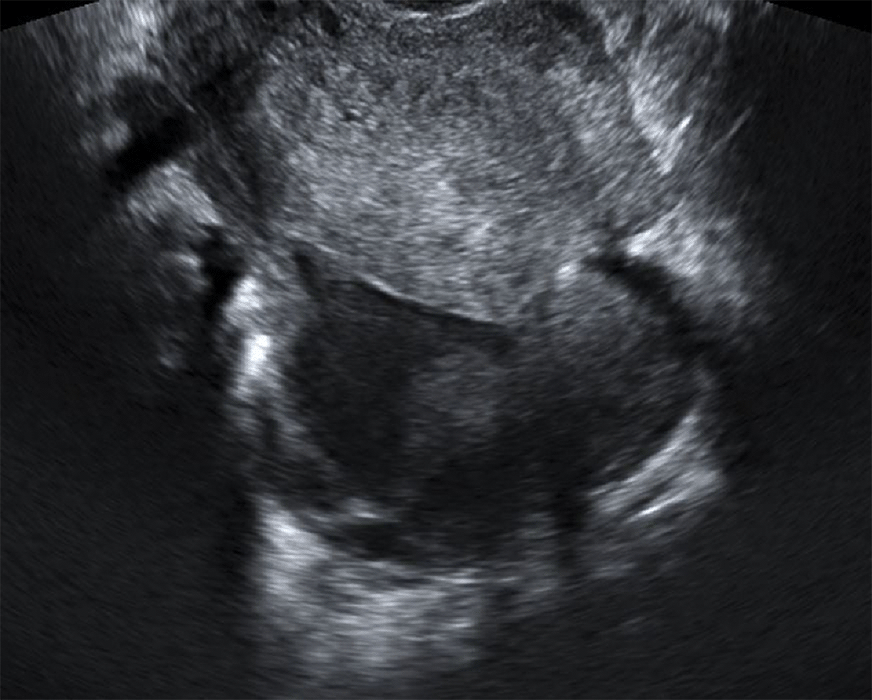

Image animée montrant l'aspect échographique d'un

abcès du cul-de-sac postérieur (de Douglas) dans le cadre d'une infection génitale haute sévère